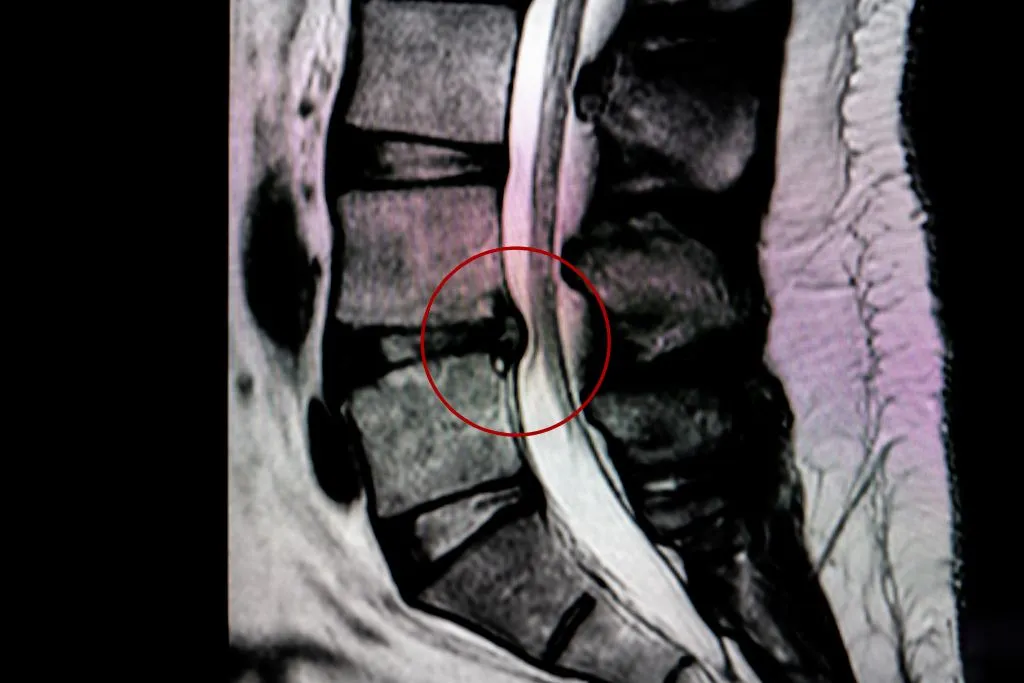

On an MRI, a herniated disc appears as a bulging or displaced section of the intervertebral disc material that extends beyond its normal boundaries.

In T2-weighted images, which highlight fluid content, the herniation is often visible as a dark mass against the brighter cerebrospinal fluid, indicating a disruption in the disc’s normal structure.

The severity of the herniation can vary, ranging from a minor bulge to a full extrusion where disc material has leaked out.

Understanding MRI Images: Normal Vs. Herniated Disc

A normal spinal disc appears as a well-defined, uniformly shaped structure with smooth edges and adequate spacing between adjacent vertebrae.

In T2-weighted MRI images, healthy discs have a bright central area (nucleus pulposus) and a darker, well-contained outer ring (annulus fibrosus), indicating the balance of fluid and structural integrity.

In contrast, a herniated disc shows an irregular shape with a portion of the disc extending beyond its normal boundary.

When evaluating an MRI scan, a doctor will assess multiple factors to determine the cause of symptoms. First, they examine the alignment of the spine and the integrity of the intervertebral discs.

Any bulging, herniation, or signs of degeneration such as decreased disc height or darkened nucleus pulposus can indicate potential sources of pain.

Doctors also check for nerve involvement by looking at the neuroforamina and spinal canal. If a herniated disc is pressing on a nerve root, it may correlate with symptoms such as radiating pain, numbness, or weakness in the limbs.